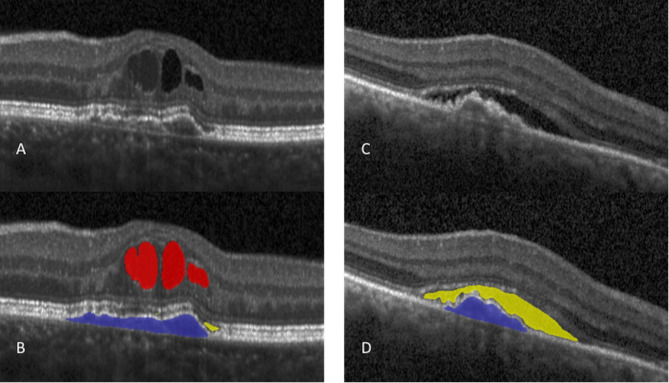

Methods: This is a retrospective real-world study performed in a tertiary center in Brazil, including patients with nAMD. Spectral-domain optical coherence tomography (Spectralis, Heidelberg Engineering, Germany) images were processed at baseline and over 2 years of follow-up. Demographic and clinical data were collected. A deep learning algorithm (Fluid Monitor, RetInSight, Austria) was used to automatically quantify intraretinal fluid (IRF), subretinal fluid (SRF) and pigment epithelial detachment (PED). A longitudinal panel regression model and Log-Rank test were performed to assess the correlation between fluid volumes and treatment frequency, visual outcomes, macular atrophy (MA) and subretinal fibrosis (SF) development.

Results: Ninety-nine eyes from 84 patients were included. Fifty-eight eyes were treatment-naïve. Higher IRF and PED in the 6 mm area were correlated with worse visual outcomes over a 2-year follow-up (p = 0.01 and p < 0.001, respectively). Higher IRF, SRF and PED were correlated with an increased risk of SF development (p < 0.001, p = 0.049 and p = 0.02 respectively). MA development showed no significant correlation with higher IRF, SRF nor PED in this analysis. Higher SRF volume correlated with a greater number of required intravitreal injections over 2-years.